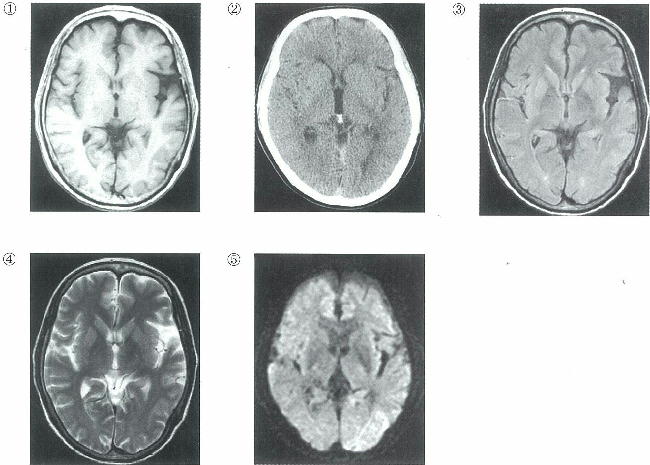

頭部の画像を別に示す。

頭部単純MRIのT1強調像はどれか。

a ①

b ②

c ③

d ④

e ⑤

○ a

正解 a